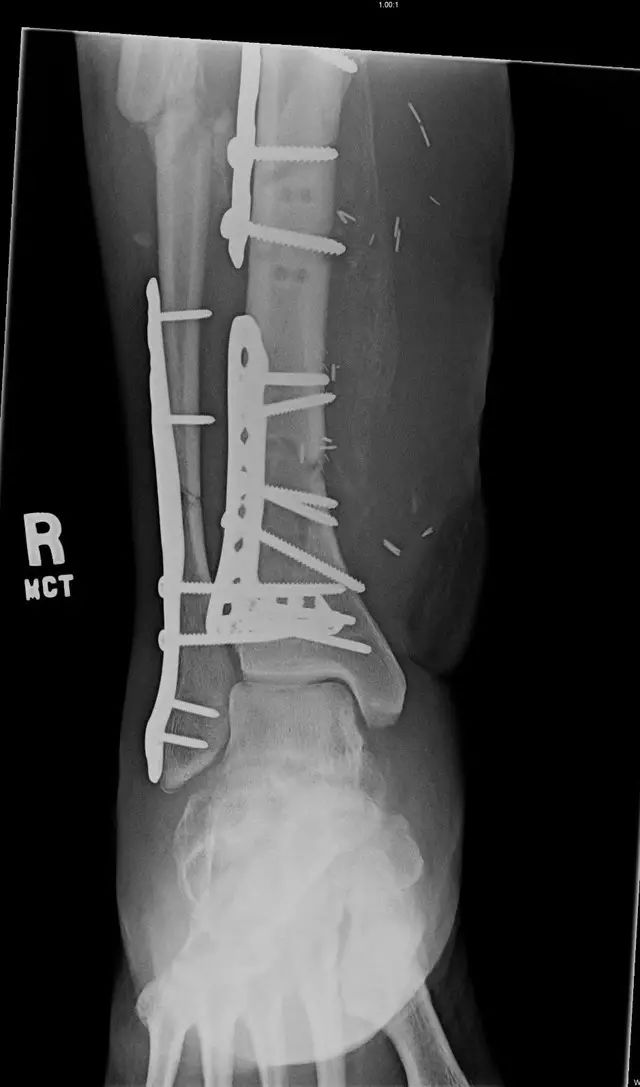

33 岁男性,车祸多发伤。左踝严重污染,几乎环形创口,胫骨远端 20 cm 缺损

游离骨块生理盐水灌洗,保持湿润,4 小时内紧急手术。术中对创口和游离骨块各用 12L 生理盐水灌洗,彻底清创。外固定支架固定,创口松散地缝合

原计划 48 小时再次灌洗,因身体情况不稳定,10 天后再次进手术室清创灌洗,方法如前;48 小时后进行了第三次灌洗,然后进行了内固定,闭合创口。

3 个月后创口无感染迹象,骨折处无压痛

6 个月后,骨折线模糊,独立行走

18 个月恢复工作